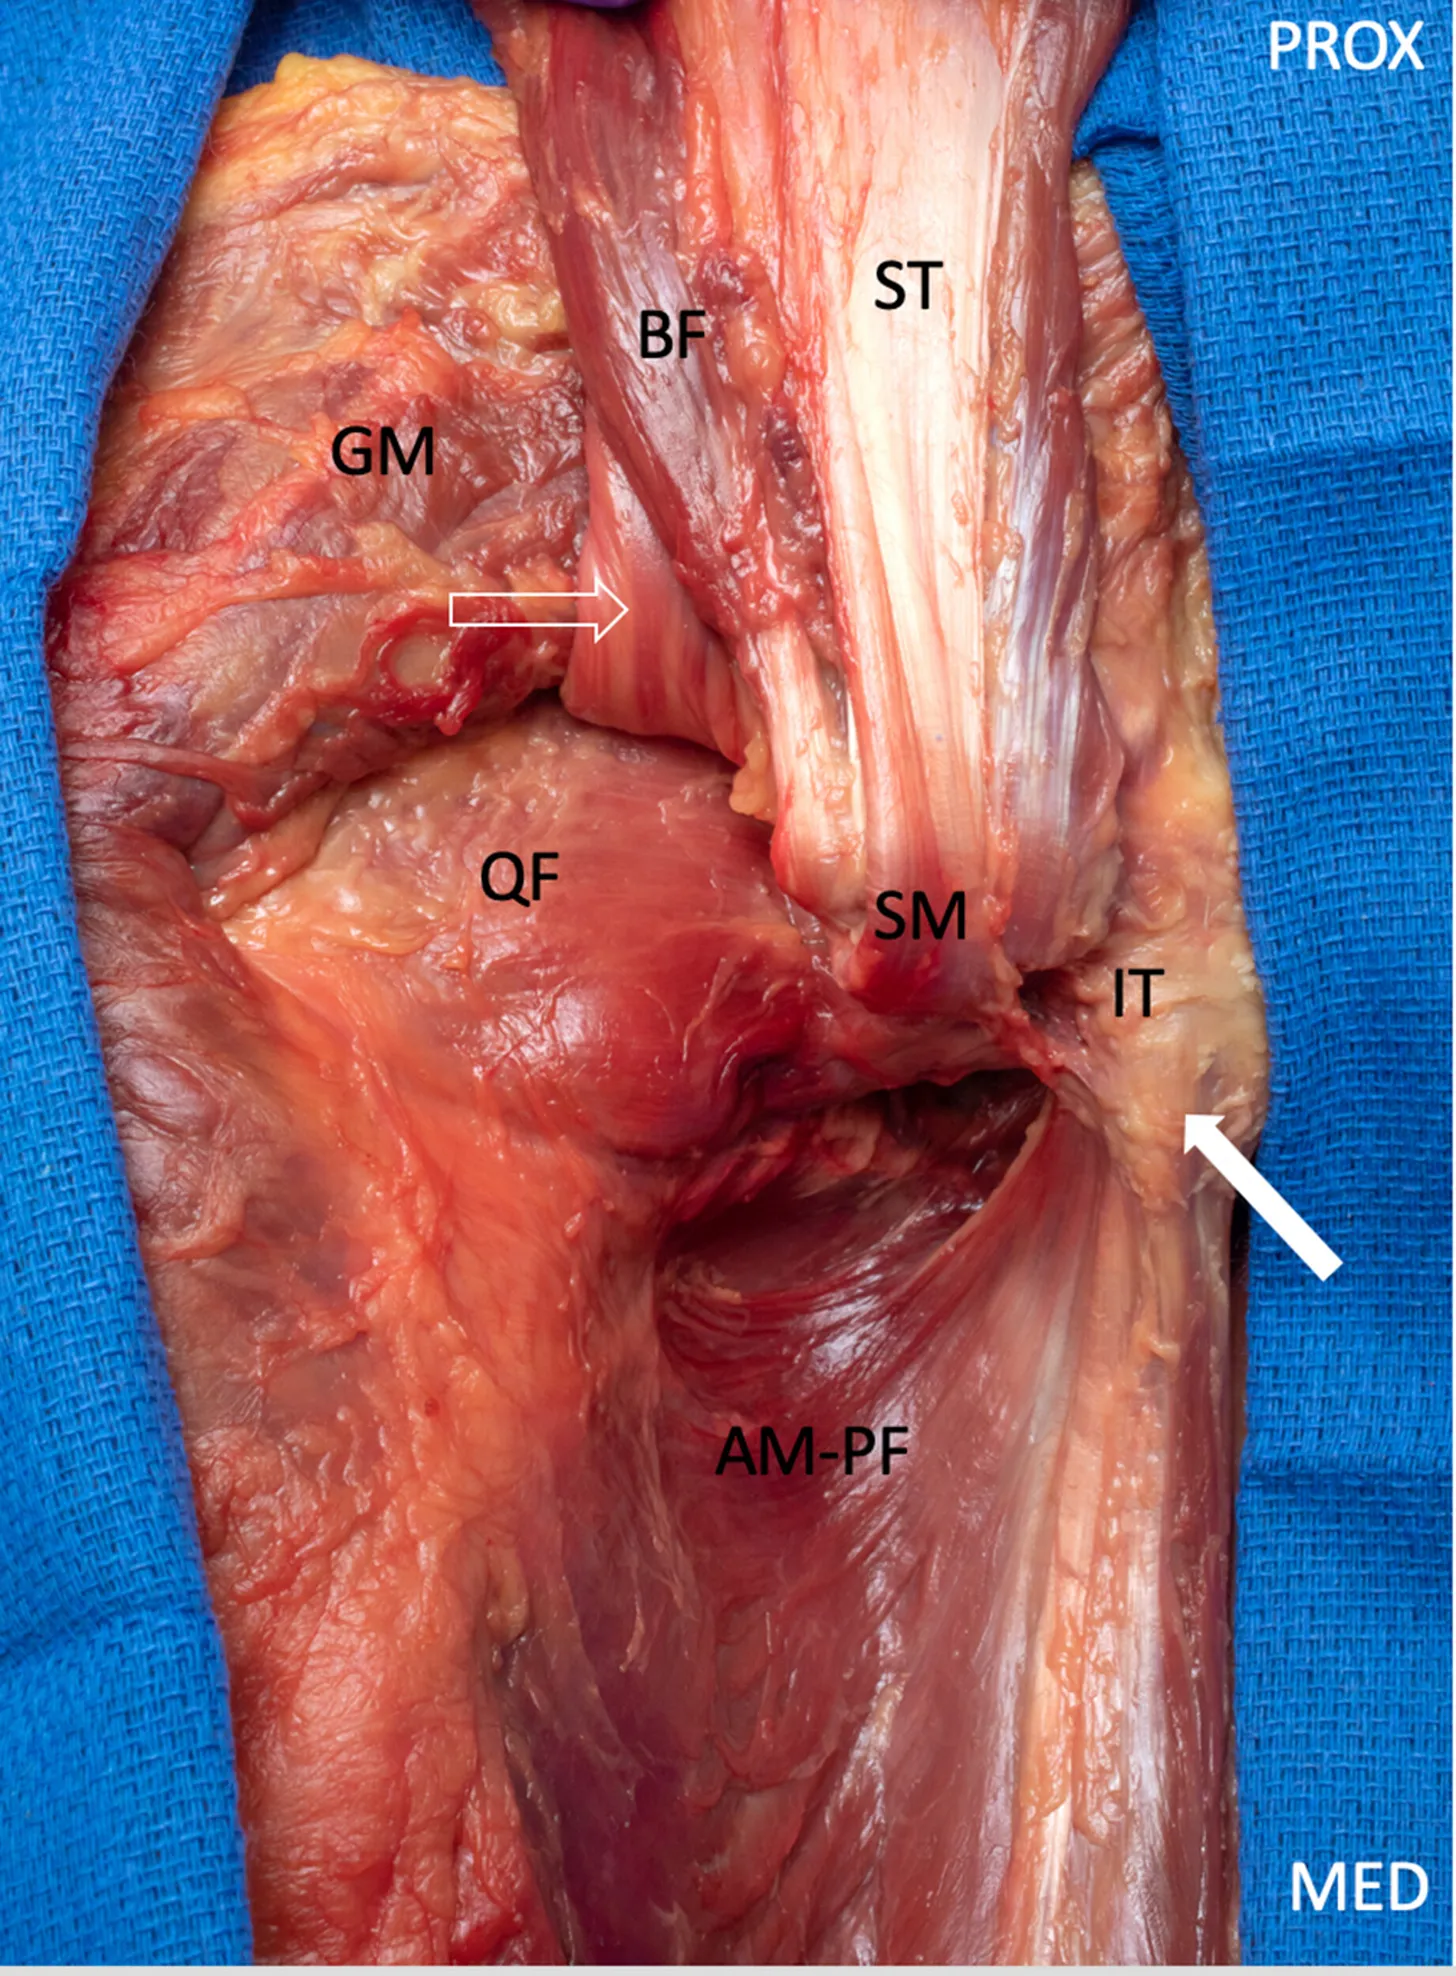

Preparación cadavérica de la cadera posterior que demuestra la inserción del tendón de origen isquiocondíleo del aductor mayor (flecha) en la tuberosidad isquiática, situada inferomedialmente con respecto a las inserciones en la tuberosidad isquiática de los tendones proximales de los isquiotibiales (los cuales se encuentran seccionados distalmente y retraídos proximal y lateralmente para permitir la visualización del tendón de origen isquiocondíleo del aductor mayor).

El nervio ciático (SN) se visualiza solo de forma parcial, ya que la imagen se obtiene desde una perspectiva medial.

ST: semitendinoso; BF: bíceps femoral; SM: semimembranoso; QF: cuadrado femoral;

GM: cara profunda reflejada del músculo glúteo mayor;

IT: tuberosidad isquiática; MED: medial; PROX: proximal.